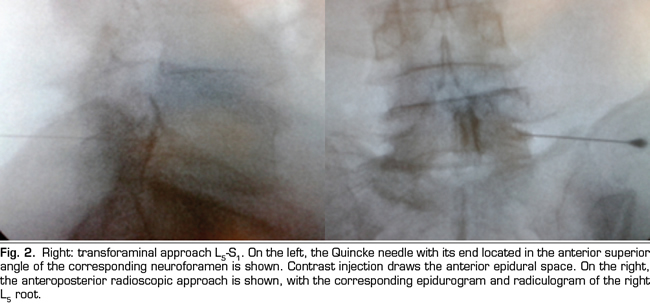

The final position of the needle in the oblique view was the subpedicular zone, while in the lateral view was the anterior superior angle or the roof of the neuroforamen, in the so-called safety triangle (Figure 2). The contrast volume injected was equivalent to the performed in the interlaminar group, obtaining a radiculogram and epidurogram after the injection (Figure 2). The solution of betamethasone was the same used in the interlaminar group, injecting the total volume of the solution in one or two levels, depending on clinical criteria.